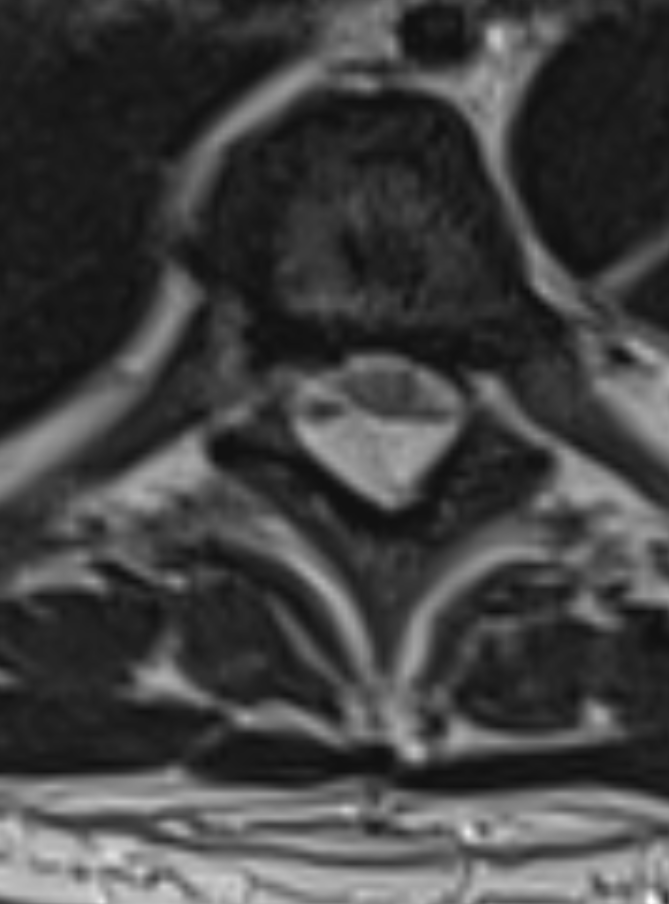

Nice one, but without the axial images, it’s hard to get the dissected aorta.. you wrote there are no herniated disc, so I am wondering what was the reason for getting the enlightening axials

Exactly. Without the axial slices... great chances of missing it. That’s why axial images should span the entire spine when youn don't see nothing (like disc pathology) at the sagittal

- Aortic dissection + pleural effusion